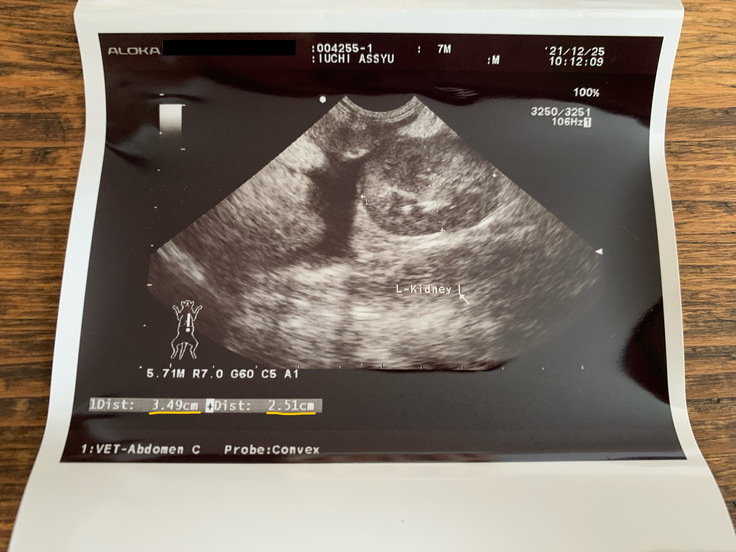

2021/12/25

『治療すること』を諦められず、藁にもすがる思いで、片道3時間かけ新薬での治療に協力している病院へ。アッシュ、長時間の移動でストレスをかけてしまってごめんね。

体重2.75キロ。改めて追加で必要な検査を実施。腹水も採取できたため検査へ。エコーでは腹部に3cmほどのしこりがあることもわかりました。確定診断につながる検査結果が出るのは約1週間後ですが、今ある検査結果と子猫であることを考えても、FIPであることはほぼ確実であるため、治療開始できることを伝えられ、早期から新薬での治療を始めることを決断・選択しました。

アッシュは腹水だけでなく、腹部のしこり(肉芽形成の可能性)・肝機能低下も見られており、ウェットとドライの混合タイプであるため、ウェットタイプの治療より多く薬が必要とのことでした。新薬は84日間、毎日同じ時間に内服し続ける治療です。